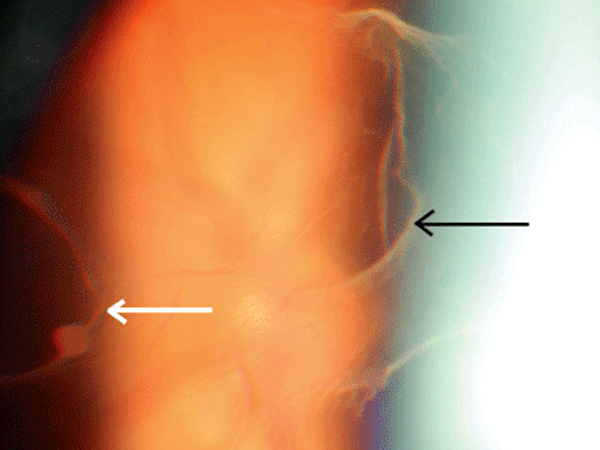

In alcune occasioni, il vitreo può separarsi dalla retina provocando una rottura e sanguinolento vitreale. Questo causa la comparsa di nuovi corpi mobili.

Se non trattato la rottura retinica può evolvere in distacco retinico.

Esame del fondo oculare

E' sufficiente a determinare la presenza di corpi mobili vitreali, l'associazione di un distacco di vitreo e di possibili rotture retiniche periferiche.